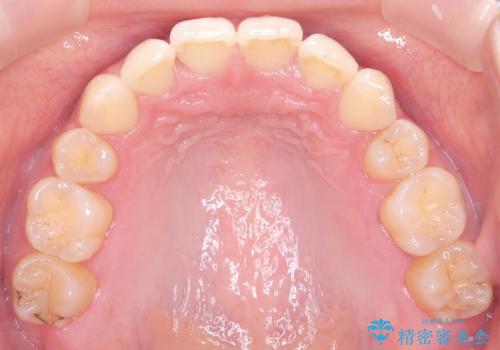

- 患者様は、上下の噛み合わせのバランスが悪く、特に上顎の前歯の突出を気にされて来院されました。診査の結果、下顎の歯並びに合わせて上顎を後方へ移動させる必要があると判断し、上顎の小臼歯2本を抜歯することを提案しました。目立たない矯正を希望されたため、**インビザライン(マウスピース矯正)**を選択。計画的にスペースを作りながら、バランスの取れた歯並びを目指しました。

治療はまず、上顎の小臼歯を2本抜歯し、そのスペースを利用して前歯を後方へ移動させました。インビザラインはアタッチメントを併用し、より効率的に歯を動かせるよう調整。定期的なチェックとアライナーの交換を続け、約3年かけて理想的な歯並びと噛み合わせを実現しました。治療後はリテーナーを使用し、安定した状態を維持。患者様からは「口元がスッキリし、横顔の印象も変わった」と嬉しいお声をいただきました。